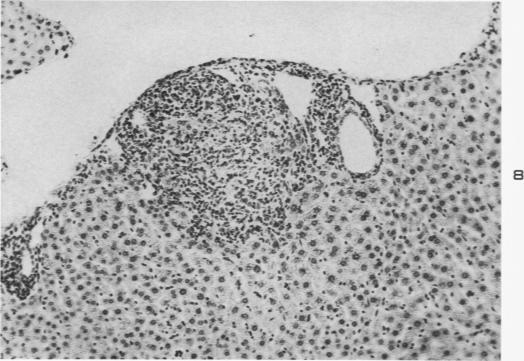

Experimental moniliasis in mice.

Am J Pathol. 1955 Sep-Oct;31(5):859-73.